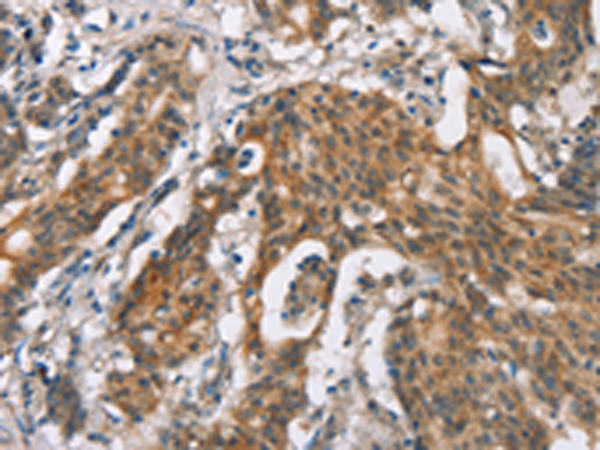

分类: 科研抗体货号: P11612别名: ik3-2; C20orf150; dJ908M14.2应用: IHC反应种属: Human, Mouse